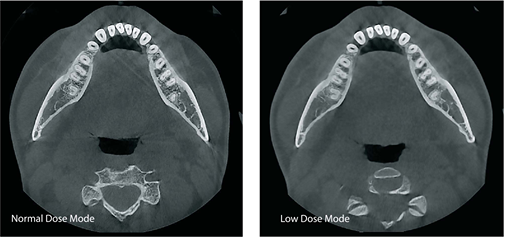

- How Much Radiation? (Radiation Dose): You want to keep the radiation as low as possible for your patients. Look for systems that:

- Have Low-Dose Settings: Some machines have special settings that use less radiation for certain types of scans.

- Use Pulsed Exposure: This way of taking the X-ray can lower the overall dose.

- Let You Adjust the FOV: Scanning only what you need to see helps reduce radiation.